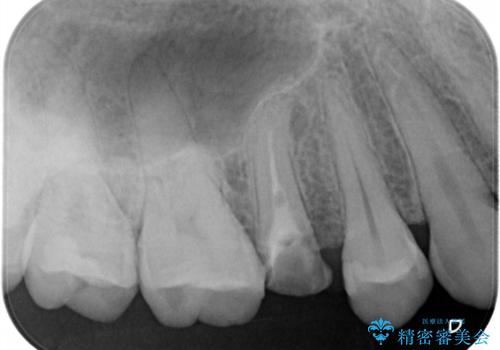

- 「左右どちらとも、どこかが痛む」とご来院された患者様です。

他院で虫歯治療を複数行っており、原因となりうる歯がいくつかありました。まずレントゲン上最もあやしい右上から治療開始しました。右上の歯は1本割れていたため、部分矯正で引っ張り出しました。

他院で虫歯治療を複数行っており、原因となりうる歯がいくつかありました。まずレントゲン上最もあやしい右上から治療開始しました。

右上の被せものを除去したところ、中で歯が割れていたため、部分矯正で引っ張り出すことになりました。